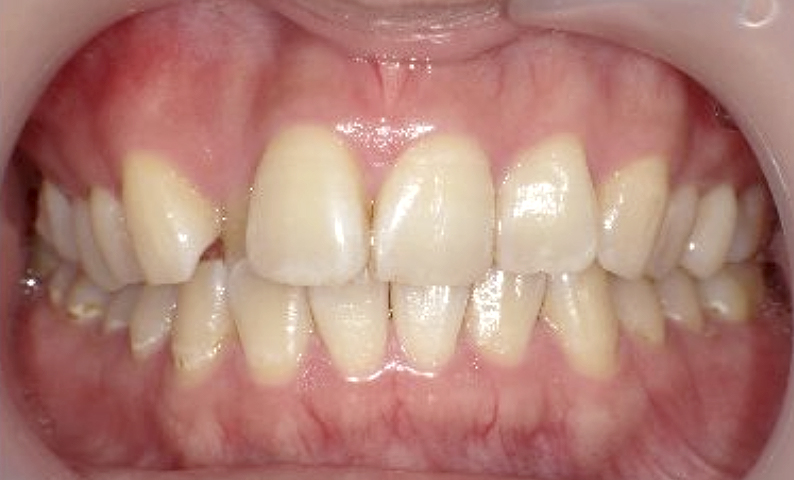

症例_002 下顎だけの部分矯正

治療期間:4ヶ月金額:30万円+税女性前歯のガタガタ下の前歯だけ

| Before | After |

|---|---|

|